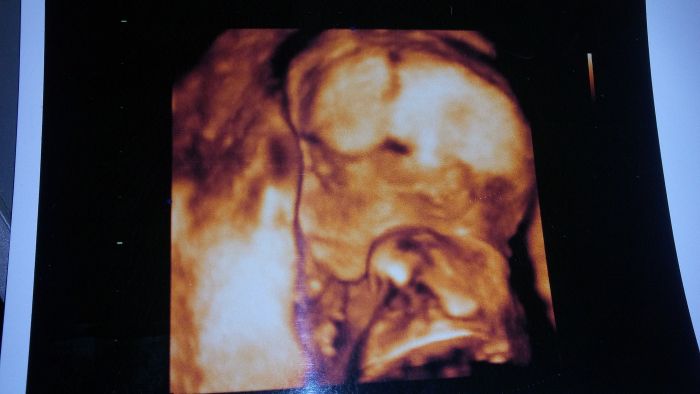

Ahoj holky tak jsme po utz a už to máme na 150% holčičku, měla vaječníky nebo co to :D Ale fotit se nechce Terezka naše, měla hlavu furt v placentě a ne a ne se ukázat má 300g a jsem 19+5 a dle MS 20+1tt ale říkal že tonje normalka fotky nic moc no jak rikam nechtěla se ukázat za celé tehu jsem pribrala 2,1 kg a teď za ty 3 týdny 1,3 kg :D tlak normalka nizsi, přítel no chudak asi ani nevěděl na co se kouká a 3D říkal že je nechutné :D atbmunukazuju jen černobílé :D jinak na další kontrolu 24.11. A na cukr nvm? To asi až pak nebo vůbec?

A tady jsou některé fotky ze screeningů